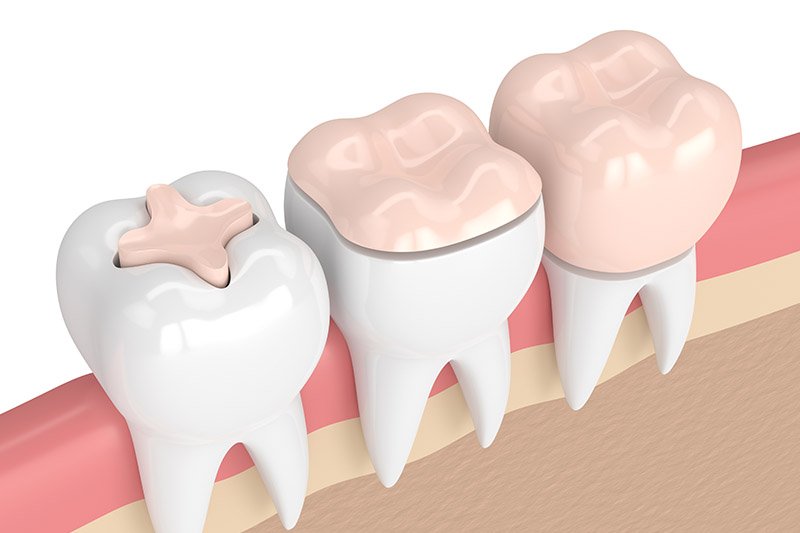

ODONTOIATRIA CONSERVATIVA

- Diagnosi precoce della carie mediante transilluminazione laser

- Valutazione del rischio di carie basso, moderato ed alto

- Tecniche restaurative adesive dirette e indirette